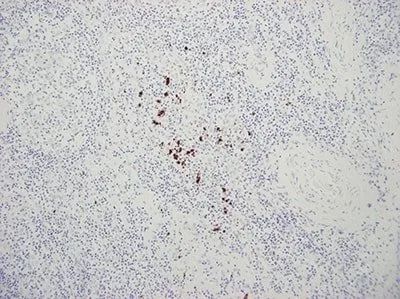

這張低質(zhì)量染色的切片(HPV)有凸起及背景染色。

🙅 錯(cuò)誤:不平整,貼合不平整的切片的染色不均勻,背景會(huì)被不同程度染色。